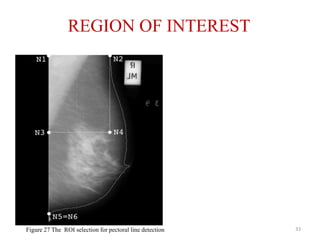

REGION OF INTEREST

33Figure 27 The ROI selection for pectoral line detection